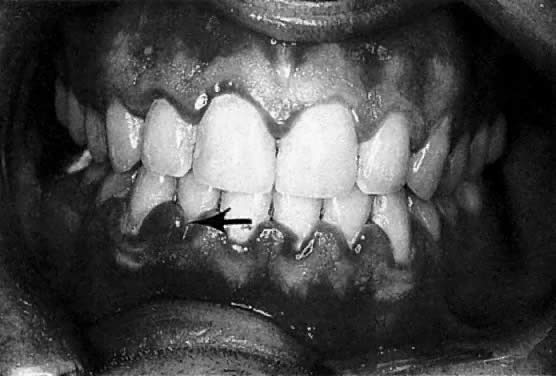

The frequently observed gingival changes that occur during pregnancy were reported as early as 1877.1 For many years, however, there have been questions about the reported prevalence of periodontal disease in pregnancy, the role that local and hormonal factors may have in the pathogenesis, and the implication of certain microorganisms in the etiology of this disease. Based on clinical observation, the reported frequency of so-called pregnancy gingivitis ranges from 35%2 to 100%3 (Fig. 1). This variation may be a reflection of both the populations studied and the clinical parameters used.

Fig. 1. Moderately severe pregnancy gingivitis in a 30-year-old patient during the eighth month of pregnancy.

According to studies using well-defined indices, gingival inflammation is a heightened or exacerbated response to dental plaque during a period of progesterone and estrogen imbalance.4 In addition, the effect of pregnancy on pre-existing gingival inflammation is first noticeable in the second month of gestation and peaks in the eighth month (see Fig. 1). During the last month of gestation, a definite decrease in gingivitis generally occurs, and the gingival status immediately postpartum is found to be similar to that at the second month of pregnancy.3 The greatest relative increase in gingivitis during pregnancy is observed around the anterior teeth, although the molars demonstrate the highest gingivitis scores throughout pregnancy. The papillae (interproximal areas) are the most frequent sites of gingival inflammation both during pregnancy and after parturition.